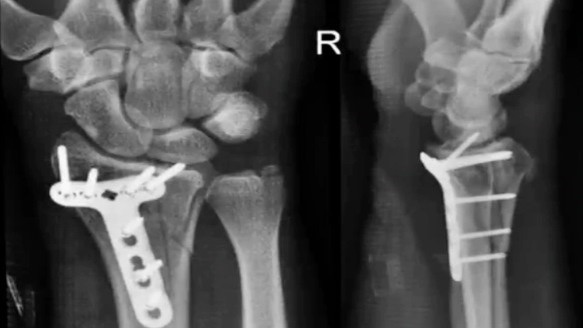

"Con el impacto de la caída (a casi 80 kilómetros por hora), mi muñeca derecha sufrió una fractura distal fragmentada del radio, que requirió cirugía", escribe en sus comentarios al final del video en Youtube. "Me instalaron una placa de titanio y siete tornillos, y me dieron de alta la tarde siguiente".